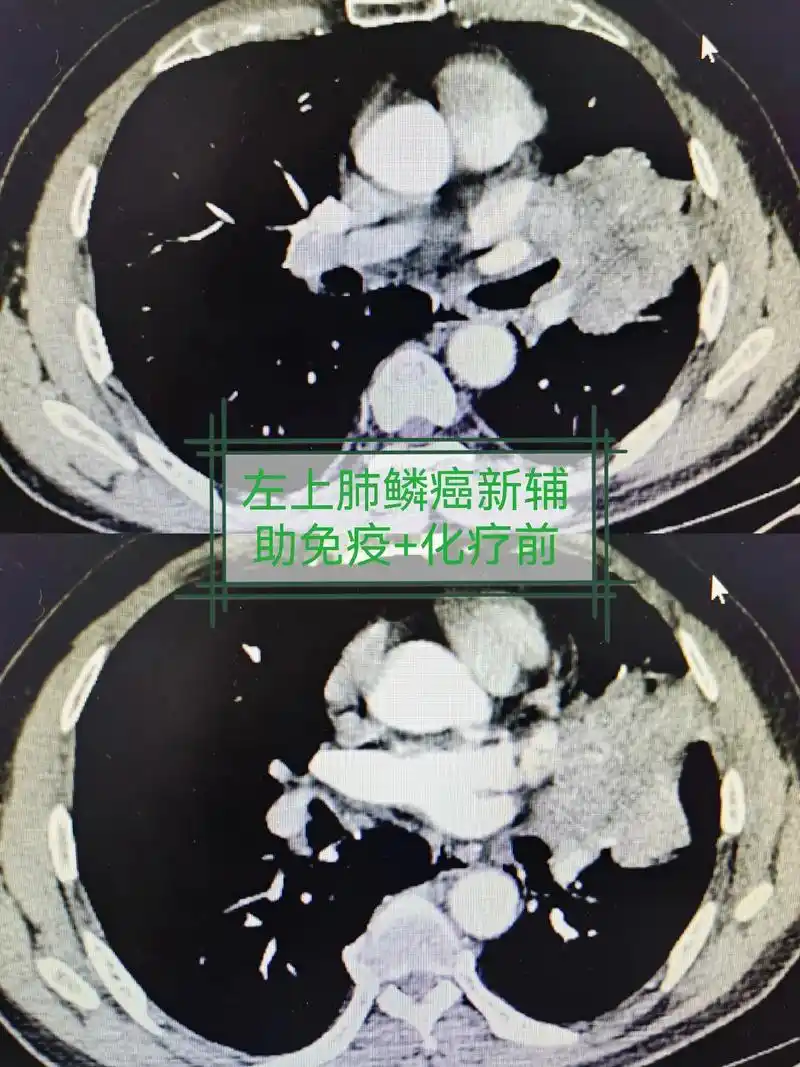

肺癌 #守护健康 #希望能帮到你 局部晚期肺癌,新辅助治疗 - 抖音

左图为晚期肺癌,右图为早期肺癌(5年前)但是天不遂人愿,半年后,一次